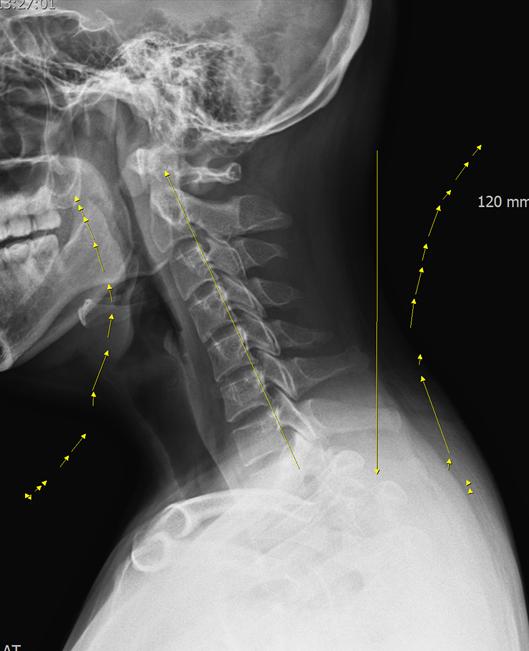

“You Can See It Even Without Reading the X-ray”

Sometimes, you don’t need to be able to read an X-ray to see the problem.

In forward head posture, the patient’s neck visibly shifts forward, and the normal C-shaped cervical curve becomes straightened or even reversed.

This is what many people call “tech neck” or “forward head posture (FHP)”.